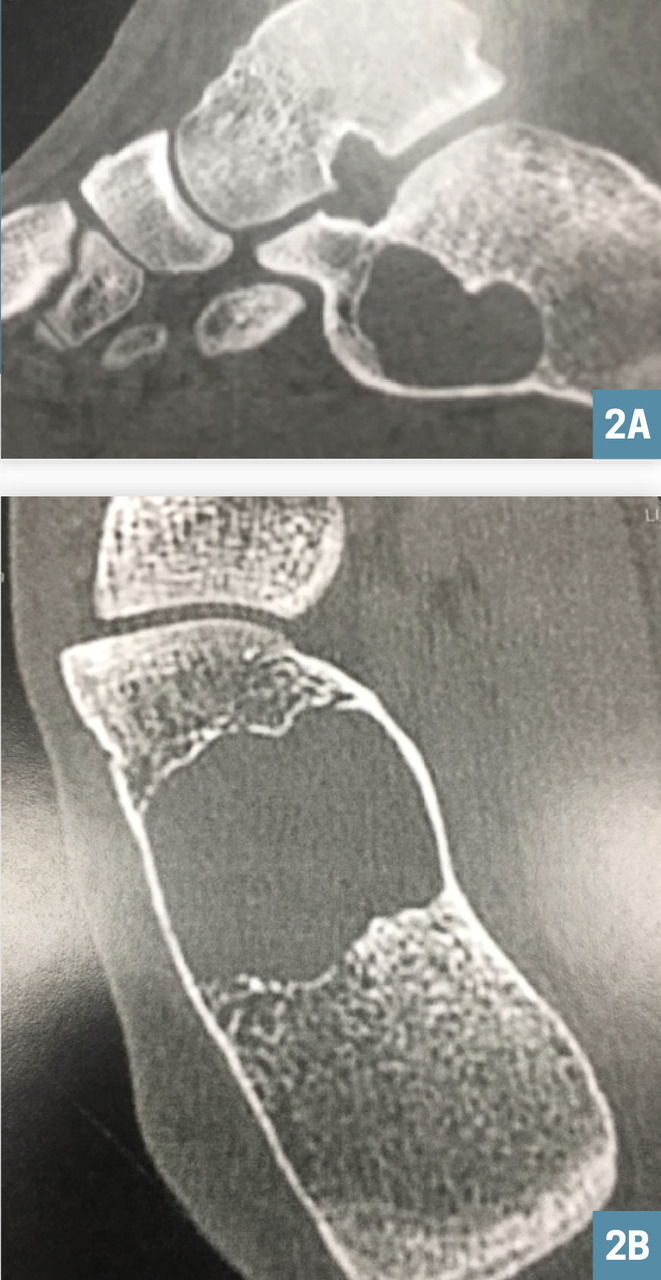

Ces examens permettent de poser le diagnostic de kyste osseux essentiel calcanéen, lésion bénigne qui ne nécessitera qu’une surveillance radiologique (fig. 2A et 2B).

Dans la plupart des cas, les radiographies standard sont suffisantes pour faire le diagnostic. Elles montrent une lésion lacunaire à contours nets, centrale, parallèle à l’axe de l’os et se situant au contact d’un cartilage de croissance. Les corticales sont respectées. Le kyste est généralement unique et peut contenir de fins septas internes. Les autres examens (scintigraphie, tomodensitométrie, imagerie par résonance magnétique [IRM]) sont inutiles. La ponction biopsique est rarement indiquée.